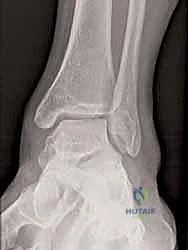

* الأشعة السينية أثناء الوقوف (Weight-bearing X-rays): ضرورية جداً لتقييم محاذاة العظام تحت تأثير وزن الجسم. يتم البحث عن اتساع في المسافة الصافية الإنسية (Medial Clear Space widening)، مما يدل على تمزق رباط الدالية العميق.

* الأشعة السينية مع الإجهاد (Stress Radiographs): يتم التقاط الصور أثناء تطبيق قوة معينة على الكاحل لإظهار عدم الاستقرار الخفي الذي لا يظهر في الصور العادية.